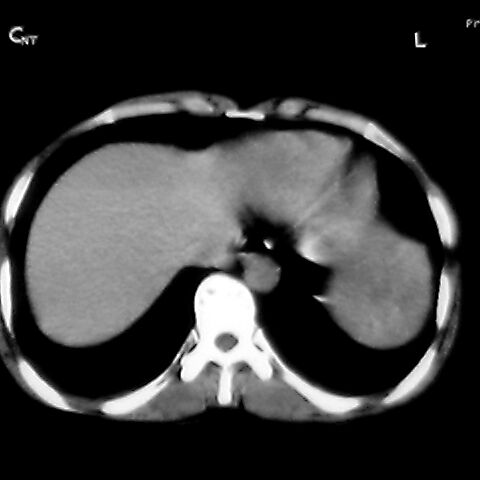

女 48岁 食道癌术前体检发现脾占位。

脾胀内部巨大低密度肿块,边界清或不清,中心坏死,轻度增强,内见散在钙化,结合食道癌病史多考虑:转移癌.

1肝右下叶小囊肿2右肾上极囊肿或错构瘤3脾脏不典型血管瘤可能性大.

脾脏低密度灶伴钙化,增强化明显,中心见液化坏死灶,强化延时明显。考虑血管瘤。转移瘤待排。

右肾见类圆形低密度影.结合病史.脾及右肾转移性ca可能性大

1,脾血管瘤。2,右肝,右肾小囊肿。